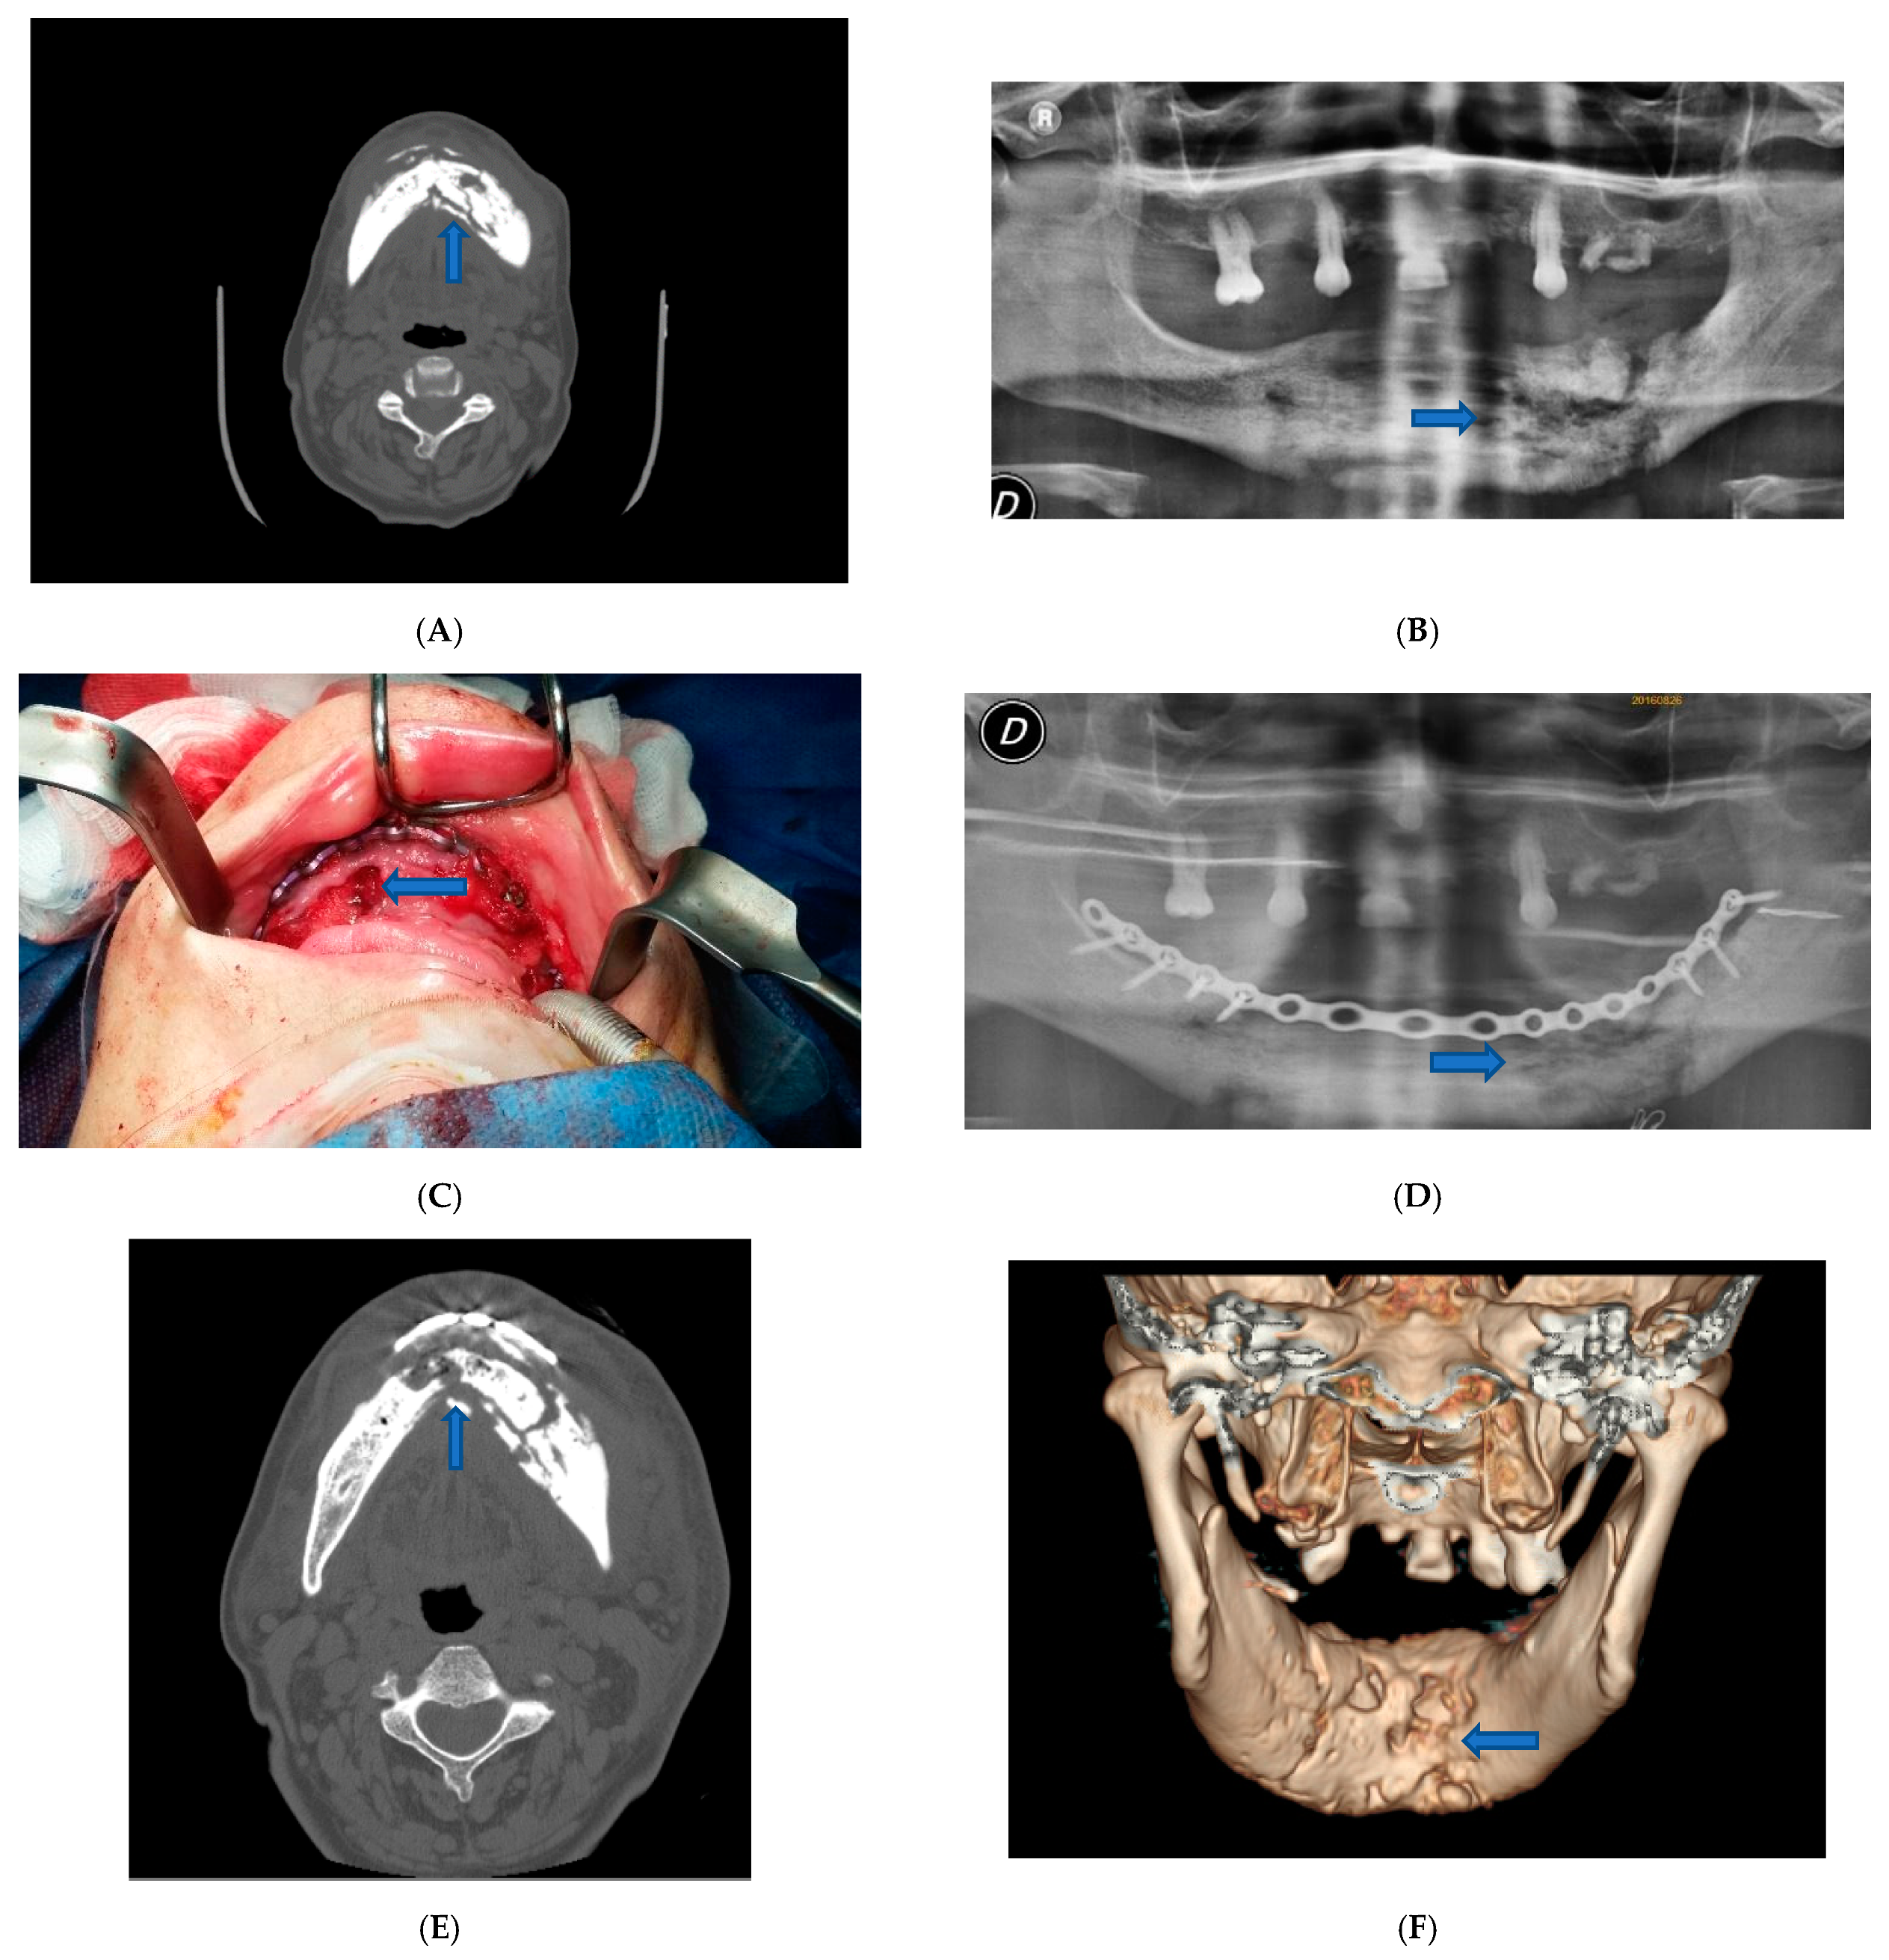

The second case was an 80-years-old woman of Caucasian origin who referred bilateral pain in the mandibular body. The patient was treated with continuous therapy with bisphosphonates.

In this second case, despite the absence of fractures, it was decided to intervene and apply an epi-mucosal fixation because of the very high risk of pathologic fracture due to the osteonecrosis outbreak. Surgery was performed under general anesthesia. After the debridement and removal of the necrotic bone with sequestrectomy and bone trimming, also in this case we proceeded to an epi-mucosal fixation performed using SMART Lock screws and plates without elevating the mucoperiosteal flap (Figure 2C). As in the first case, we proceeded to the preparation of autologous PRF with the application of the PRF directly to the site of intervention. A vicryl polyglactin (91, 3/0) absorbable suture was used to close the flap.

Figure 2.

Patient 2. (A) Pre-operative panoramic X-ray examination showed no fractures, but there was a subversion of the normal organization of the bone. (B) Pre-operative X-Ray image showed lithic area in the lower branch. (C) Epi-mucosal fixation performed using SMART Lock screws and plates without elevating the mucoperiosteal flap. (D) Post-operative panoramic X-ray image of the dental branch revealed lithic area. (E) Post-operative CT scan Image. (F) Post-operative X-ray image.

Postoperative course was without complications. Postoperative therapy comprised oral hygiene instructions. Application of 0.2% chlorhexidine solutions twice a day, an evening application of 0.2% chlorhexidine gel upon the sutured incision lines, and administration of a non-steroidal anti-inflammatory aid (Ketoprofen 80 mg) for five consecutive days. Even in this case, antibiotic therapy was administered in the perioperative phase, starting the night before the surgery and up to 4 days after, using 500 mg of Amoxicillin and Clavulanate every 8 h. The patient was examined for the first time one week later and then 3 and 6 months after surgery (Figure 2D–F).

For case two, patient physical examination showed no obvious swelling of the face. Oral examination showed no irregularities.

CT examination showed that there was a lithic area in the lower branch of the mandible. Although there were no fractures, the subversion of the normal organization of the bone exposed the patient to a high-risk for pathological fracture. Radiographic evidence showed an extensive osteolysis compatible with stage 3 MRONJ (Figure 2A,B).